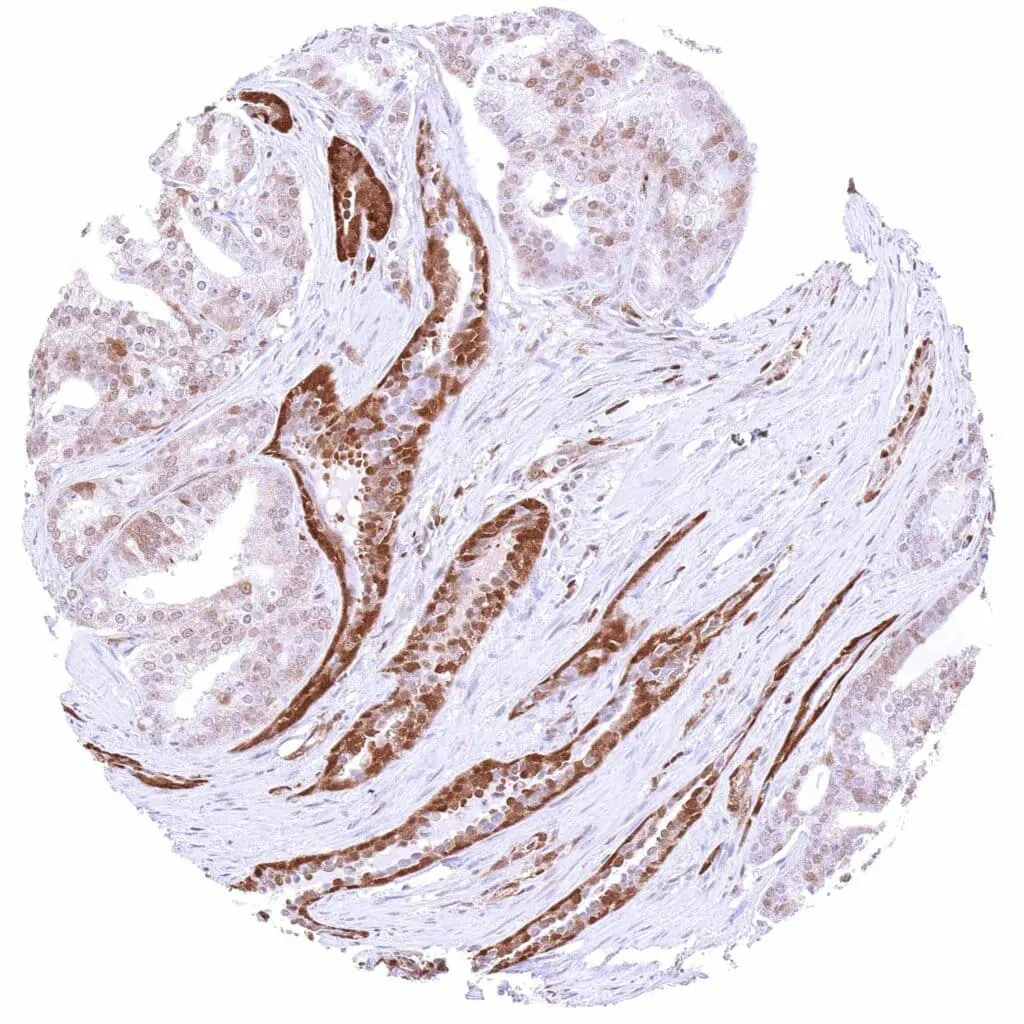

p27 Kip1 antibody [HMV3970] HistoMAX™

Breast – Invasive breast cancer of no special type (NST) with strong p27 staining of tumor cells.

Breast – Invasive lobular breast cancer with strong nuclear and cytoplasmic p27 staining of tumor cells.